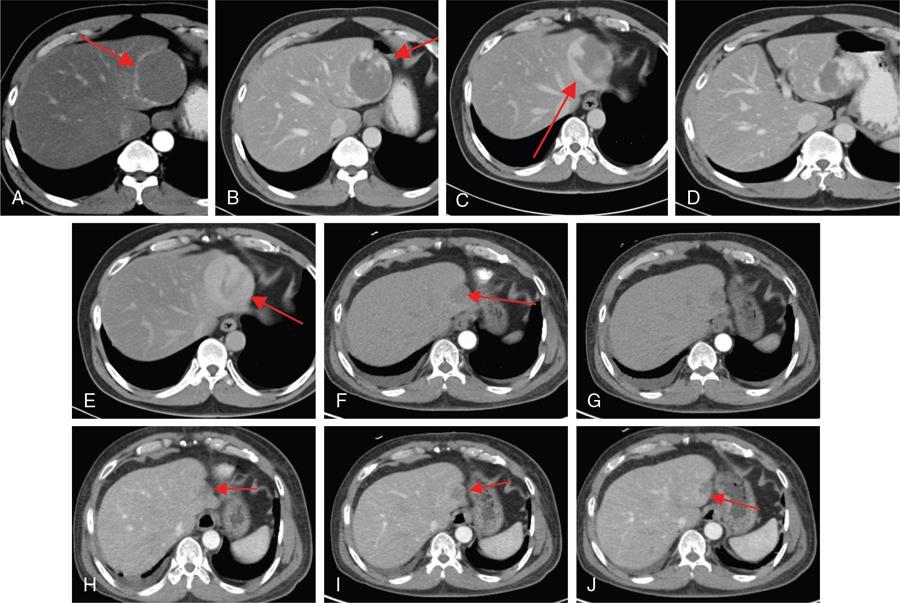

Ritu K. Kashikar, Shrinivas B. Desai, Pooja Punjani Vyas, Nilesh Doctor, Vivek Shetty Owing to advances in technology, focal liver lesions (FLLs) are increasingly encountered. Imaging particularly computed tomography (CT) and magnetic resonance imaging (MRI) play a vital role in diagnosis and characterization of FLL, thus avoiding unnecessary biopsies and interventions. Multiphase CT accurately diagnosis most liver lesions. Better soft tissue contrast and lack of ionizing radiation makes MRI a preferred modality in diagnosing FLLs. MRI with or without contrast for characterization of liver lesions regardless of preexisting liver disease has been assigned the highest rating as per American College of Radiology Appropriateness Criteria (Table 9.11.1). Solid lesions of epithelial origin Solid lesions of nonepithelial origin Pitfalls Cystic liver lesion Developmental cyst Infective cyst Miscellaneous Tmours of hepatocellular origin Tumours of nonepithelial origin Malignant cystic lesion Hepatic metastasis Ultrasound is often the initial modality for diagnosis and also the incidental detection of FLLs. Limitations to USG include the detection of small lesions less than 2 cm in size, particularly in patients who are cirrhotic or undergoing chemotherapy. Characterization of FLLs, involvement of crucial structures such as blood vessels, local staging and decisions such as operability are also not accurate with ultrasound alone and require confirmation with CT/MRI. The liver typically images in supine and left lateral positions. A curvilinear transducer with a frequency of 1.5 Hz is used. The subcostal diagonal, subcostal longitudinal or sagittal and transverse right intercostal lateral views are used. Right lobe of liver is imaged through an intercostal approach when the patient is taking deep inspiration. Subcostal view is used to image the three hepatic veins in one view. Transverse, longitudinal and oblique views of the liver are taken to image all the segments of liver. Colour and power Doppler have increased sensitivity for FLL detection, but sensitivity is still inferior to contrast-enhanced CT and MRI. The introduction of microbubble contrast agents (CAs) and the development of contrast-specific techniques have opened new perspectives in ultrasound of the liver. The technique is based on a new class of intravascular microbubble agents which contain perfluoro gases instead of air. This when combined with scanning modes sensitive to harmonic responses of microbubbles enable tissue signal suppression. The advent of the multislice technique and isotropic voxel have improved the spatial resolution of CT, allowing the recognition of small FLLs in difficult areas. Multislice CT has a sensitivity and specificity in the diagnosis of malignant FLLs of 63% and 64%, and 92 and 97%, respectively. Contrast media administration with dose based on the patient’s weight (approximately 600 mg iodine/kg of bodyweight), an iodine content of 350–400 mg/mL and a high injection rate of 4–5 mL/s are imperative to attain good contrast enhancement. Region of interest in the abdominal aorta and a threshold of 100 HU allows correct timing for threshold. A delay of approximately 18 s after the threshold provides the first arterial phase, allowing detection of hypervascular FLLs such as hepatocellular carcinoma (HCC). The late arterial phase is obtained approximately 10 s after the early arterial phase and shows progressive enhancement of hypervascular lesions, improving detection rate, while the optimal hepatic enhancement in the portal phase is reached approximately 50–60 s after the threshold. Portal venous thrombi are also best detected in this phase. The venous phase aids in the detection of washout, hepatic venous thrombosis. Delayed phase is often required in lesions such as cholangiocarcinoma and haemangioma, which show progressive enhancement (Table 9.11.2, Fig. 9.11.1). Delayed phase images are required for tumours such as cholangiocarcinoma and large haemangiomas, which reveal delayed enhancement. As mentioned previously, MRI is the modality of choice in diagnosis of FLLs. Most FLLs appear hyperintense on T2W1 images with varying intensity depending upon the water content and flow dynamics. FLLs are typically hypointense on T1W1 images with the exception of fat containing, haemorrhagic lesions and those containing chelates of metals like regenerating/dysplastic nodules. In- and opposed-phase images help in detection of intralesional fat. Diffusion-weighted images are beneficial particularly in noncirrhotic population and best suited in detection of metastasis. Postcontrast images obtained with extracellular agents are parallel to those obtained with CT (Fig. 9.11.2). The pre- and postcontrast MRI protocol is mentioned in Table 9.11.3. T2-weighted single-shot fast spin-echo (SE) T1-weighted in- and opposed-phase GRE Dynamic 3D T1-weighted FS spoiled GRE (in hepatic arterial, portal venous and equilibrium phases) There are two main categories of CAs used in liver imaging – the extracellular and the hepatocyte-specific (Fig. 9.11.3). Extracellular agents are more widely used and provide information similar to contrast-enhanced CT study. The advantage of the other category of CAs, that is, hepatocyte-specific agents, is the ability to provide this extracellular information with added benefit of delayed phase information. Tumours of hepatocellular origin with functioning hepatocytes take up and biliary excretion with take up and retain these agents appearing isointense to background liver. Lesions without functioning hepatocytes fail to retain contrast and hence appear hypointense to background liver on delayed phase. This allows better detection and characterization of focal liver lesion particularly those lesser than 2 cm (Table 9.11.4). Haemangioma is the most common benign hepatic tumour. The incidence in general population varies from 1% to 20%. Females have a higher preponderance with variable female to male ratios of 2:1 to 5:1. Imaging in particular MRI has high reliability in diagnosing classic haemangioma. The sensitivity and specificity of MRI is greater than 90% in diagnosis. The aetiology of haemangioma is unknown. Since haemangiomas are known to run in families, a genetic origin has been implicated, while other mesenchymal tumours are thought to be congenital. Most patients are asymptomatic and often the lesion is discovered as an incidental finding. Pain in the right upper abdomen is the most common complaint; others include loss of appetite, nausea, vomiting and abdominal discomfort. Symptoms are usually seen in large haemangiomas or those with complications. Liver function tests and tumour markers like AFP and CA19.9 are within normal limits. Blood-filled cavities of varying sizes lined by flat endothelial cells and supported by fibrous connective tissue are seen on histology. Three histological subtypes have been described: the capillary haemangioma, the cavernous haemangioma and the sclerosing haemangioma. The imaging features of a haemangioma depend on its size; typical haemangiomas are mostly less than 3 cm in diameter. Haemangiomas are hyperechogenic, homogeneous lesion presenting a posterior acoustic enhancement (Fig. 9.11.3). The hyperechogenicity of haemangiomas is related to the interfaces between vascular spaces, fibrous stroma and the slow blood flow. Typically, haemangiomas have slow flow and hence do not show vascularity on colour or power Doppler. The sensitivity and specificity of ultrasound in differentiating haemangioma from other malignant lesions are high, with values of approximately 94.1% and 80%, respectively, for lesions less than 3 cm in diameter. Unlike HCC, no flow is seen on colour Doppler. A peripheral echogenic rim around hypoechoic lesions can suggest haemangioma. On the contrary, perilesional hypoechoic rim called the target sign is seen in lesions such as metastasis (Table 9.11.5). Adenomas can be distinguished on the basis of the absence of posterior acoustic enhancement and characteristic pattern of peripheral vascularity seen in adenoma. Another differential diagnosis to be considered is focal nodular hyperplasia (FNH), which has the characteristic ‘spoke-wheel sign’. Contrast-enhanced ultrasound (CEUS) improves specificity for the diagnosis of haemangioma. The vascularity pattern with contrast-enhanced USG is similar to that seen with CT. The typical hemangioma (HH) shows peripheral nodular enhancement in the arterial phase with complete (but sometimes incomplete) centripetal filling in the portal venous and late phases. This particular pattern of enhancement helps in differentiating haemangiomas from other lesions like adenomas, FNH, HCC or metastasis. This characteristic enhancement pattern has a sensitivity of 98% for histologically proven HH. One should be aware that an HH can rarely have a centrifugal enhancement. Computed tomographic (CT) findings consist of a hypoattenuating lesion on nonenhanced images. Haemangiomas show peripheral discontinuous nodular enhancement on arterial phase of dynamic contrast-enhanced CT. The density of the nodules is equivalent to that of the aorta. Centripetal filling with is seen on venous phase, which progresses to uniform enhancement. The enhancement persists on delayed phase (Fig. 9.11.4). Washout of contrast on delayed phase is not seen in haemangioma and if seen, alternate diagnosis must be considered. This classical pattern of enhancement cannot be highlighted in very small lesions of less than 5 mm, which can be difficult to characterize. In patients with severe fatty infiltration of the liver, HH can appear hyperdense relative to the adjacent liver parenchyma on nonenhanced scan. Haemangiomas are hyperintense on T2-weighted images, which is identical to that of cerebrospinal fluid. T2 hyperintense signal is classically described as ‘light bulb bright’. Malignant lesions of the liver do not appear as bright on T2W1 images. They appear hypointense to adjacent liver on T1-weighted images. Long relaxation T2W1 images further improve accuracy in diagnosis of haemangiomas and help in differentiation from metastasis. Haemangiomas, unlike other liver lesions retain hyperintense signal on long relaxation T2W1 images. A threshold of 112 ms has 92% accuracy, 96% sensitivity and 87% specificity for differentiating haemangiomas from metastasis. On gadolinium administration, the enhancement pattern is similar to that seen with iodinated contrast on CT. Classic enhancement pattern in combination with characteristic T2 appearance are diagnostic for haemangioma (Fig. 9.11.5). Certain pitfalls exist in diagnosing haemangiomas using gadoxetate disodium. Due to the lack of hepatocytes, haemangiomas appear hypointense to the background liver on delayed hepatocyte phase and mimicking malignant process (Table 9.11.6). Lesions shown peripheral nodular arterial enhancement (Table 9.11.7): On fluorodeoxyglucose-positron emission tomography (FDG-PET)/CT, most hepatic haemangiomas appear low-attenuation lesions with FDG avidity equal to background liver parenchyma and are easily determined to be benign. However, a small percentage of haemangiomas may be FDG-avid. If an FDG-avid hepatic lesion demonstrates the characteristic enhancement pattern, this is consistent with an FDG-avid haemangioma. Technetium-99m pertechnetate-labelled red blood cell scintigraphy has high specificity in the diagnosis of haemangiomas. In this technique, there is decreased activity in haemangiomas on early images and increased activity on delayed blood pool images. Therefore, radionuclide scintigraphy has a sensitivity of 78% and an accuracy of 80% and may be a valuable tool when the diagnosis cannot be achieved with other imaging modalities. Large haemangiomas are often heterogeneous with internal clefts and septae. They are termed as giant haemangiomas when they exceed 4 cm in diameter. Discrepancies are there in definition with some authors defining giant haemangiomas as lesions greater than 6 cm or 12 cm in diameter. These may cause symptoms of abdominal pain and distension. These haemangiomas demonstrate changes such as haemorrhage, thrombosis, extensive hyalinization, liquefaction and fibrosis. The central cleft-like area may be due to cystic degeneration or liquefaction. On USG, they reveal heterogeneous echotexture. They are hypoattenuating and heterogeneous on nonenhanced CT with central areas of low attenuation. After intravenous administration of contrast material, the typical early, peripheral and globular enhancement is observed. These may show irregular or ‘flame-shaped’ discontinuous peripheral enhancement as opposed to typical nodular enhancement pattern seen in smaller haemangiomas. Although centripetal pattern of enhancement is seen during the venous and delayed phases, the filling-in incomplete. Central scars are defined in this subset of haemangiomas (Fig. 9.11.6). At MRI, T2-weighted images show a markedly hyperintense cleft-like area and some hypointense internal septa within a hyperintense mass. On delayed phase, incomplete filling and central scar are seen similar to CT (Fig. 9.11.7). Complications include intratumoural haemorrhage, inflammatory changes or consumptive coagulopathy (Kasabach–Merritt syndrome). These may warrant management such as arterial embolization or resection. This pattern is seen 16% of all haemangiomas, and is seen more often in small haemangiomas (42% of haemangiomas) <1 cm in diameter. CT and MRI show immediate homogeneous enhancement at arterial phase CT or contrast-enhanced MRI. The size of the blood spaces is the reason for difference in enhancement pattern. Smaller the lesion, smaller the size of blood spaces and faster the rate of spread of contrast material. These lesions usually show perilesional halo of hyperenhancement on the late arterial phase, which is believed to be due to arteriovenous shunting. Rapid arterial enhancement makes these haemangiomas difficult to distinguish from hypervascular metastasis (Table 9.11.8). However, washout of contrast is seen from haemangiomas on delayed phase (Fig. 9.11.8). Hepatic haemangiomas rarely demonstrate calcifications, while haemangiomas in other locations frequently demonstrate phleboliths. Calcified haemangiomas are mostly found incidentally. Calcifications may occur in the marginal or central portion of the lesion and consists of multiple spotty calcifications, which correspond to phleboliths. However, large, organized calcifications are also possible. Some calcified haemangiomas may demonstrate poor enhancement. Hyalinized hepatic haemangiomas are rare. It has been suggested that hyalinization represents an end stage of haemangioma evolution. These haemangiomas are usually asymptomatic. The radiological features of a haemangioma are completely altered ones hyalinization occurs; hence biopsy is often mandatory for diagnosis. Hyalinized haemangiomas show only slight high signal intensity on T2W1 images. There is lack of early enhancement on dynamic contrast-enhanced images (Fig. 9.11.9). Fluid–fluid levels within haemangiomas are very rare. Fluid–fluid levels are seen both with CT and MRI with inferior layer representing the red blood cells and superior layer unclotted serous blood. Dependent hyperdensity/T1 hyperintensities can be seen corresponding with dependent haemorrhage. Pedunculated haemangiomas are very rare. They can be asymptomatic or complicated by subacute torsion and infarction. Typical enhancement pattern and signal on T1 and T2W1 images are clues to the diagnosis. Capsular retraction is usually associated with malignant tumours such as cholangiocarcinoma, epithelioid haemangioendothelioma or metastases. Rarely, it has been seen in haemangiomas. A possible mechanism could be fibrous degeneration. Multiple haemangiomas are seen in 10% of cases and usually show classical imaging features. Fatty infiltration of liver may alter the imaging appearances of lesions. Haemangiomas appear slightly hyperechoic, isoechoic or hypoechoic relative to the fatty liver. At nonenhanced CT, the lesion may be hyperattenuating relative to the liver. Contrast-enhanced CT shows peripheral enhancement and delayed filling, an appearance similar to that of a haemangioma in a normal liver. Haemangiomas are less common in setting of cirrhosis and may be difficult to diagnose due to sclerosis. Complications are seen in 4.5%–19.7% and often seen in large lesions such as inflammation, coagulation within can lead to systemic disorders, haemorrhage would lead to haemoperitoneum, volvulus and adjacent organ compression. Irrespective of the size, treatment is indicated only for haemangiomas with significant symptoms, those developing complications, or when there is an inability to exclude malignancy. Attempt should be made to exclude other causes of the patient’s symptoms. The term focal nodular hyperplasia (FNH) was introduced in 1958 by Edmondson. In 1995, the International Working Party classified FNH with other regenerative lesions, and not a neoplastic lesion. It is defined as a nodule consisting of normal appearing hepatocytes occurring in a histologically normal liver. It is the second most common tumour of the liver after haemangioma with a reported prevalence of 0.9%. The lesion is more commonly seen in females with female to male ratio of 8:1. Multiplicity is seen in 20% of patients. The combination of multiple FNH lesions and haemangiomas is considered to be multiple FNH syndrome. Vascular malformation and vascular injury have been suggested as the underlying mechanism. An association with steroids has been denied more recently. FNH has been classified as classic and nonclassic varieties. These have been discussed in Table 9.11.9. Classic FNH is characterized by abnormal nodular architecture, malformed vessels and cholangiolar proliferation. Nonclassic FNH lesions lack one of the following classic features – nodular abnormal architecture or malformed vessels – but always show bile ductular proliferation. Classic FNH on gross appearance shows lobulated contours with multiple nodules surrounded by fibrous septae originating from a central scar, which contains a vascular malformation. On histopathology, nodular hyperplastic parenchyma is seen in classic FNH. Circular or short fibrous septae surround these nodules completely or incompletely. Thickening of the hepatic plates is seen. Fibrous connective tissue, cholangiolar proliferation with surrounding inflammatory infiltrates and malformed arteries, capillaries, vascular channels of undetermined type and veins are seen in the central scar. The arterial blood in FNH shows centrifugal distribution from anomalous central arteries. Fatty infiltration is seen in approximately 50% of lesions, while signs of hepatic steatosis are seen in approximately 20% of cases with classic FNH. Variable amounts of Kupffer cells are seen in both classic and nonclassic variants. Nonclassic FNH is heterogeneous and on gross appearance resembles adenomas in most cases, with vaguely lobulated contours and lack of a macroscopic central scar. The histology varies with subtypes. Subtypes of nonclassic FNH include telangiectatic type, mixed hyperplastic and adenomatous forms and FNH with cytologic atypia. The histological features of these are described in Table 9.11.10. At US, typical FNH is often not well visualized. The lesions may be slightly hypoechoic, isoechoic or slightly hyperechoic. The compressed liver tissue form a hypoechoic halo around the lesion, which appears more prominent in patients with fatty infiltration. A prominent central scar may improve the conspicuity of the lesions. Use of colour and power Doppler US shows vascularity in suspected FNH. On contrast-enhanced USG, FNH is hyperenhancing in the arterial and portal venous phases in more than 90% of cases. The arterial enhancement patterns include central (60%–70% of cases) or eccentric (<20% of cases) with centrifugal filling, but sometimes are homogeneous. Multiphase CT is an excellent modality for detection and characterization of FNH. These lesions classically show a lobulated contour. At unenhanced CT, the lesions are either hypoattenuating or isoattenuating to the surrounding liver. In the arterial phase, the lesions show homogeneous intense enhancement except the central scar and fibrous septa. In the portal and later phases, the lesions become more isoattenuating with the surrounding liver. The central scar reveals enhancement on delayed phase (Fig. 9.11.10). This feature helps distinguish from other lesions with central scar-like fibrolamellar carcinoma. A vascular malformation can be seen in the central scar in some cases (Fig. 9.11.11). There may be enlarged hepatic veins in the vicinity of the mass. FNH do not have portal venous drainage. The drainage is essentially into hepatic venules, hence the enlarged adjacent veins. The central scar is often not identified in small FNH lesions. In a study, 80% of FNH lesions less than 3 cm lacked visible central scar. The sensitivity and specificity of MRI in diagnosis of FNH are 70% and 98%, respectively. The central scar is more often detected with MRI than with CT (78% and 60%, respectively). FNH is typically iso- or hypointense on T1-weighted images (94%–100%) and is slightly hyperintense or isointense on T2-weighted images (94%–100%). The lesions may not be very conspicuous on T2W1 images. The central scar is hyperintense on T2-weighted images in 84% of cases. FNH shows intense homogeneous enhancement in the arterial phase. The enhancement pattern in arterial phase may be nodular, resembling a popcorn, the result of intralesional fibrous septae. Mosaic pattern of heterogeneous enhancement seen in malignant lesions is not seen in FNH. Central vascular malformation may be seen in early phases. These lesions classically fade to isointensity on delayed phase with the exception of the central scar (Fig. 9.11.12). FNH may show a pseudocapsule, which results from compression of the surrounding liver parenchyma by the FNH, perilesional vessels and inflammatory reaction. The pseudocapsule may show enhancement on delayed contrast-enhanced images. A central scar is present at imaging in most patients with FNH. The central scar is hyperintense on T2W1 and hypointense on T1W1 images. The presence of inflammation and vessels within the scar are responsible for the hyperintense signal (Fig. 9.11.13). The scar does not enhance on early phases of contrast study and shows enhancement on delayed phases of dynamic study. The scar is absent in 30% of cases. The hepatocyte-specific CA gadoxetate disodium can be useful in distinguishing FNH from other lesions like adenomas. Densely packed functioning hepatocytes and abnormal blind-ending bile ductules in FNH result in contrast retention and delayed biliary excretion. FNH often shows enhancement on delayed images using gadoxetate disodium, and along with radiating fibrous septae, it may result in a characteristic spoke-wheel appearance. On the contrary, hepatocellular adenomas (HCAs) are usually hypointense to liver on hepatocyte phase images because they lack bile ductules. Superparamagnetic iron oxide (SPIO) is a negative reticuloendothelial-specific CA taken up primarily by the hepatosplenic Kupffer cells. This agent shortens T2 relaxation time predominantly, leading to a significant decrease of SI of normal hepatic. FNH contains Kupffer cells and hence shows significant signal drop after administering SPIO. This CA is, however, not commonly used particularly with advent and increased usage of hepatocyte-specific agents (Table 9.11.11). These lesions have high signal intensity on T2-weighted images, a central scar with low signal intensity on T2-weighted images, a prominent pseudocapsule and incomplete intense enhancement of the lesion. Extreme heterogeneity can be seen in these lesions leading to difficulty in distinguishing from malignant lesions such as HCC and cholangiocarcinoma. Biopsy and histopathology diagnosis are often needed in this subset. Telangiectatic FNH may show areas of haemorrhage. A French study has reported an association of 23% between FNH and haemangiomas. The incidence of coexistence of FNH and adenoma is lower (3.6%). There have also been reports of rare associations of FNH with other types of vascular anomalies like congenital absence of the portal vein, inflammatory pseudotumours of the liver, hepatic vein thrombosis and intrahepatic arteriovenous shunting. Imaging differentials include HCA and other lesions with central scar like fibrolamellar carcinoma, HCC and giant haemangiomas (Table 9.11.12). FNH shows intense arterial phase enhancement and isodensity/isointensity on delayed phase, this feature helps in distinguishing from adenoma, which usually are hypoattenuating on the delayed phase. T1 hyperintensity seen in adenomas is not seen on FNH. Biopsy is recommended in cases where radiological features are atypical and distinguishing from malignant lesions like HCC cannot be made on the basis of imaging findings alone. As there is no risk of malignant transformation and complications are rare, FNH does not need treatment. Patients with large FNH causing compression of adjacent organs or occurrence of torsion in a pedunculated FNH may need surgical resection. Also, patients with diagnostic dilemma may be considered as surgical candidates. Adenoma is a less common benign primary neoplasm of the liver. Women of childbearing age taking oral contraceptives are considered at highest risk; however, it can occur in other women as well as men. Hepatic adenomas (HAs) were particularly associated with the use of older generation of OC pills with high-oestrogen content. Adenomas have also been reported to occur in men secondary to anabolic steroid/androgen use. Clomiphene, danazol and testosterone in patients with Fanconi anaemia (FA) and without FA, Klinefelter’s syndrome, glycogen storage disorders (GSDs) I, III and IV, alcohol and metabolic syndrome are other hormonal therapies and conditions associated with adenoma. Development of >10 adenomas in a patient is defined as hepatocellular adenomatosis (Fig. 9.11.14). Germline mutations of hepatocyte nuclear factor (HNF)-1 alpha and patients with type 3 maturity onset diabetes of young (MODY-3) may predispose. HCA has been categorized into three distinct subtypes based on genetic and pathologic features. These have been discussed in Table 9.11.13. Some exhibit both β-catenin activation and inflammatory features. Patients are usually asymptomatic at the time of diagnosis but some present with abdominal pain, haemorrhage, abnormal liver function tests or seldom with a palpable mass. HCA associated with haemorrhage may present with acute abdominal pain, elevated liver enzymes and hypovolemic shock. Signs of chronic anaemia and/or ‘systemic inflammatory syndrome’, characterized by fever, leukocytosis and elevated serum levels of C-reactive protein can be seen in patients with inflammatory HCA. Inflammatory HCAs are associated with a definitive increased risk of bleeding (>30%) and a risk of malignant transformation (5%–10%). The highest predilection for malignant transformation of all HCAs is seen in β-catenin activated subtype. On gross appearance, adenomas are well-circumscribed often encapsulated lesions with size varying between 1 and 30 cm. Lesions may be solitary or multifocal. They typically arise in nonfibrotic liver, however, the inflammatory subtype has been reported in the background of cirrhosis The cut surface of HA may be tan-yellow or red-brown depending upon the presence of steatosis or peliosis/haemorrhage/old haemorrhage, respectively. Sheets of benign-appearing hepatocytes with interspersed thin-walled, unpaired arteries are classically seen in HCA. Other variable features are steatosis, inflammatory cell infiltrate, sinusoidal dilatation, myxoid changes and presence of pigments such as bile pigment, lipofuscin or Dubin–Johnson-like pigment (Table 9.11.14). The typical small HCA is isoechoic in comparison to the surrounding liver parenchyma. Adenomas with high lipid content are hyperechoic on ultrasound. Intratumoural haemorrhage can also result in increased echogenicity and heterogeneity, or cystic areas. Calcifications are seen as hyperechoic foci with acoustic shadowing. Peripheral peritumoural vessels and intratumoural vessels with a flat continuous or triphasic form are seen on colour Doppler. FNH does not show this pattern of vascularity and hence this finding may be useful in distinguishing the two disease entities. On contrast-enhanced USG, arterial phase reveals centripetal or diffuse enhancement. Telangiectatic HCA with or without inflammation typically exhibit iso- or hyperenhancement in comparison to the surrounding liver parenchyma. Hypoenhancement is seen in portal venous phase with delayed washout in all subtypes. USG and contrast-enhanced USG features of histologic subtypes have been described. HNF-1α-inactivated HCAs are hyperechoic due to fat content and may be misdiagnosed as haemangiomas. The enhancement pattern is however that of arterial enhancement. With venous washout in contrast to haemangiomas which show portal venous hyperenhancement. On CEUS, telangiectatic HCA with or without inflammatory changes shows central multilocular vessel supply similar to FNH. These lesions might show centrifugal hyperenhancement during the early arterial phase which may persist on portal venous phase. Nevertheless, most adenomas are not specifically diagnosed at US and are usually further evaluated with CT or MRI. Multiphase CT is a good diagnostic modality in diagnosis of HCA. Fat or haemorrhage can easily be identified on unenhanced images. CT evidence of fat within the adenoma is seen in only about 10% of cases. Lesions show strong arterial enhancement and subcapsular feeding vessels. Enhancement is more heterogeneous in larger tumours and those with internal haemorrhage. The enhancement usually does not persist in adenomas because of arteriovenous shunting (Fig. 9.11.15). MRI is the modality of choice in diagnosis of adenomas and distinguishing various subtypes. Although the lesions can reveal varying signal on T1W1 images, recent reports have suggested that most adenomas are bright on T1-weighted images, 77% of cases in a study by Paulson et al. Other studies have, however, lesser incidence of T1 hyperintensity varying from 35% to 59%. Heterogeneous signal on TW1 images may be due to areas of increased signal intensity resulting from fat (36%–77% of cases in different series) and haemorrhage (52%–93%). Forty-seven to seventy-four per cent of HCAs are predominantly hyperintense relative to liver on T2-weighted images (Fig. 9.11.16). Majority of lesions are, however, heterogeneous owing to areas of haemorrhage and necrosis. Contrast-enhanced dynamic MR study shows early enhancement with peripheral subcapsular vessels. MR appearances can vary depending on the histological subtype (Table 9.11.15). On plain MRI, inflammatory HCA is often hyperintense on T2W images and hypointense on T1W sequence corresponding to areas of sinusoidal dilatation and inflammatory infiltrates. Foci of fat appear as areas of signal drop on opposed-phase images. They are hypervascular masses with persistent enhancement on dynamic study. Variable update of contrast especially at the periphery may be seen on hepatobiliary phase. Marked T2 hyperintense signal with persistent delayed enhancement has high sensitivity and specificity of 85% and 87%, respectively, for the diagnosis of inflammatory subtype. Peripheral hyperintensity on T2W1 images reflects the abnormal ductal reaction with altered biliary excretion and has been described as ‘atoll sign’ (Fig. 9.11.17).

CT